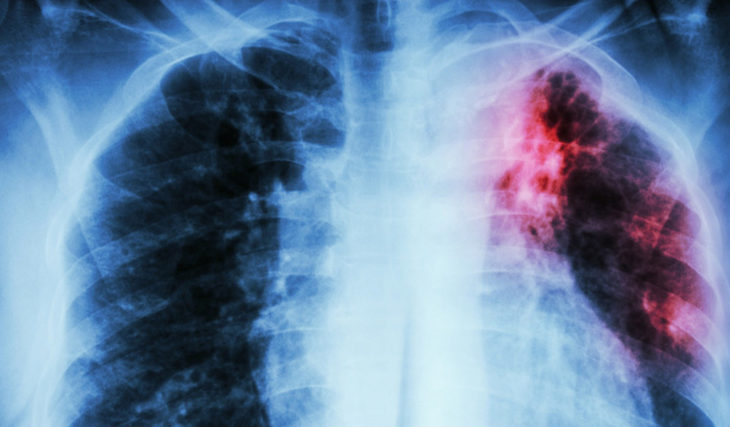

Во владивостокской школе выявлен случай туберкулеза

В школе №82 во Владивостоке (микрорайон Снеговая Падь) зафиксирован случай заболевания туберкулезом, сообщает otvprim.ru